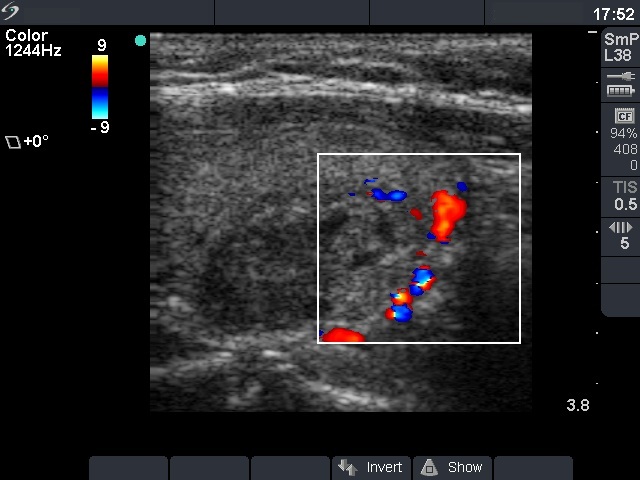

Clinical presentation: a 40-year-old woman was sent for ethanol sclerotherapy. Her thyroid cyst was evacuated three times but after each occasion the cyst got refilled within a week. FNAC resulted in a benign cystic lesion.

First row: before the first session of sclerotherapy. There was a cystic nodule in the left lobe with the dimensions of 32x27x42 mm (width x depth x length). 5 sessions of ethanol sclerotherapy was administered.